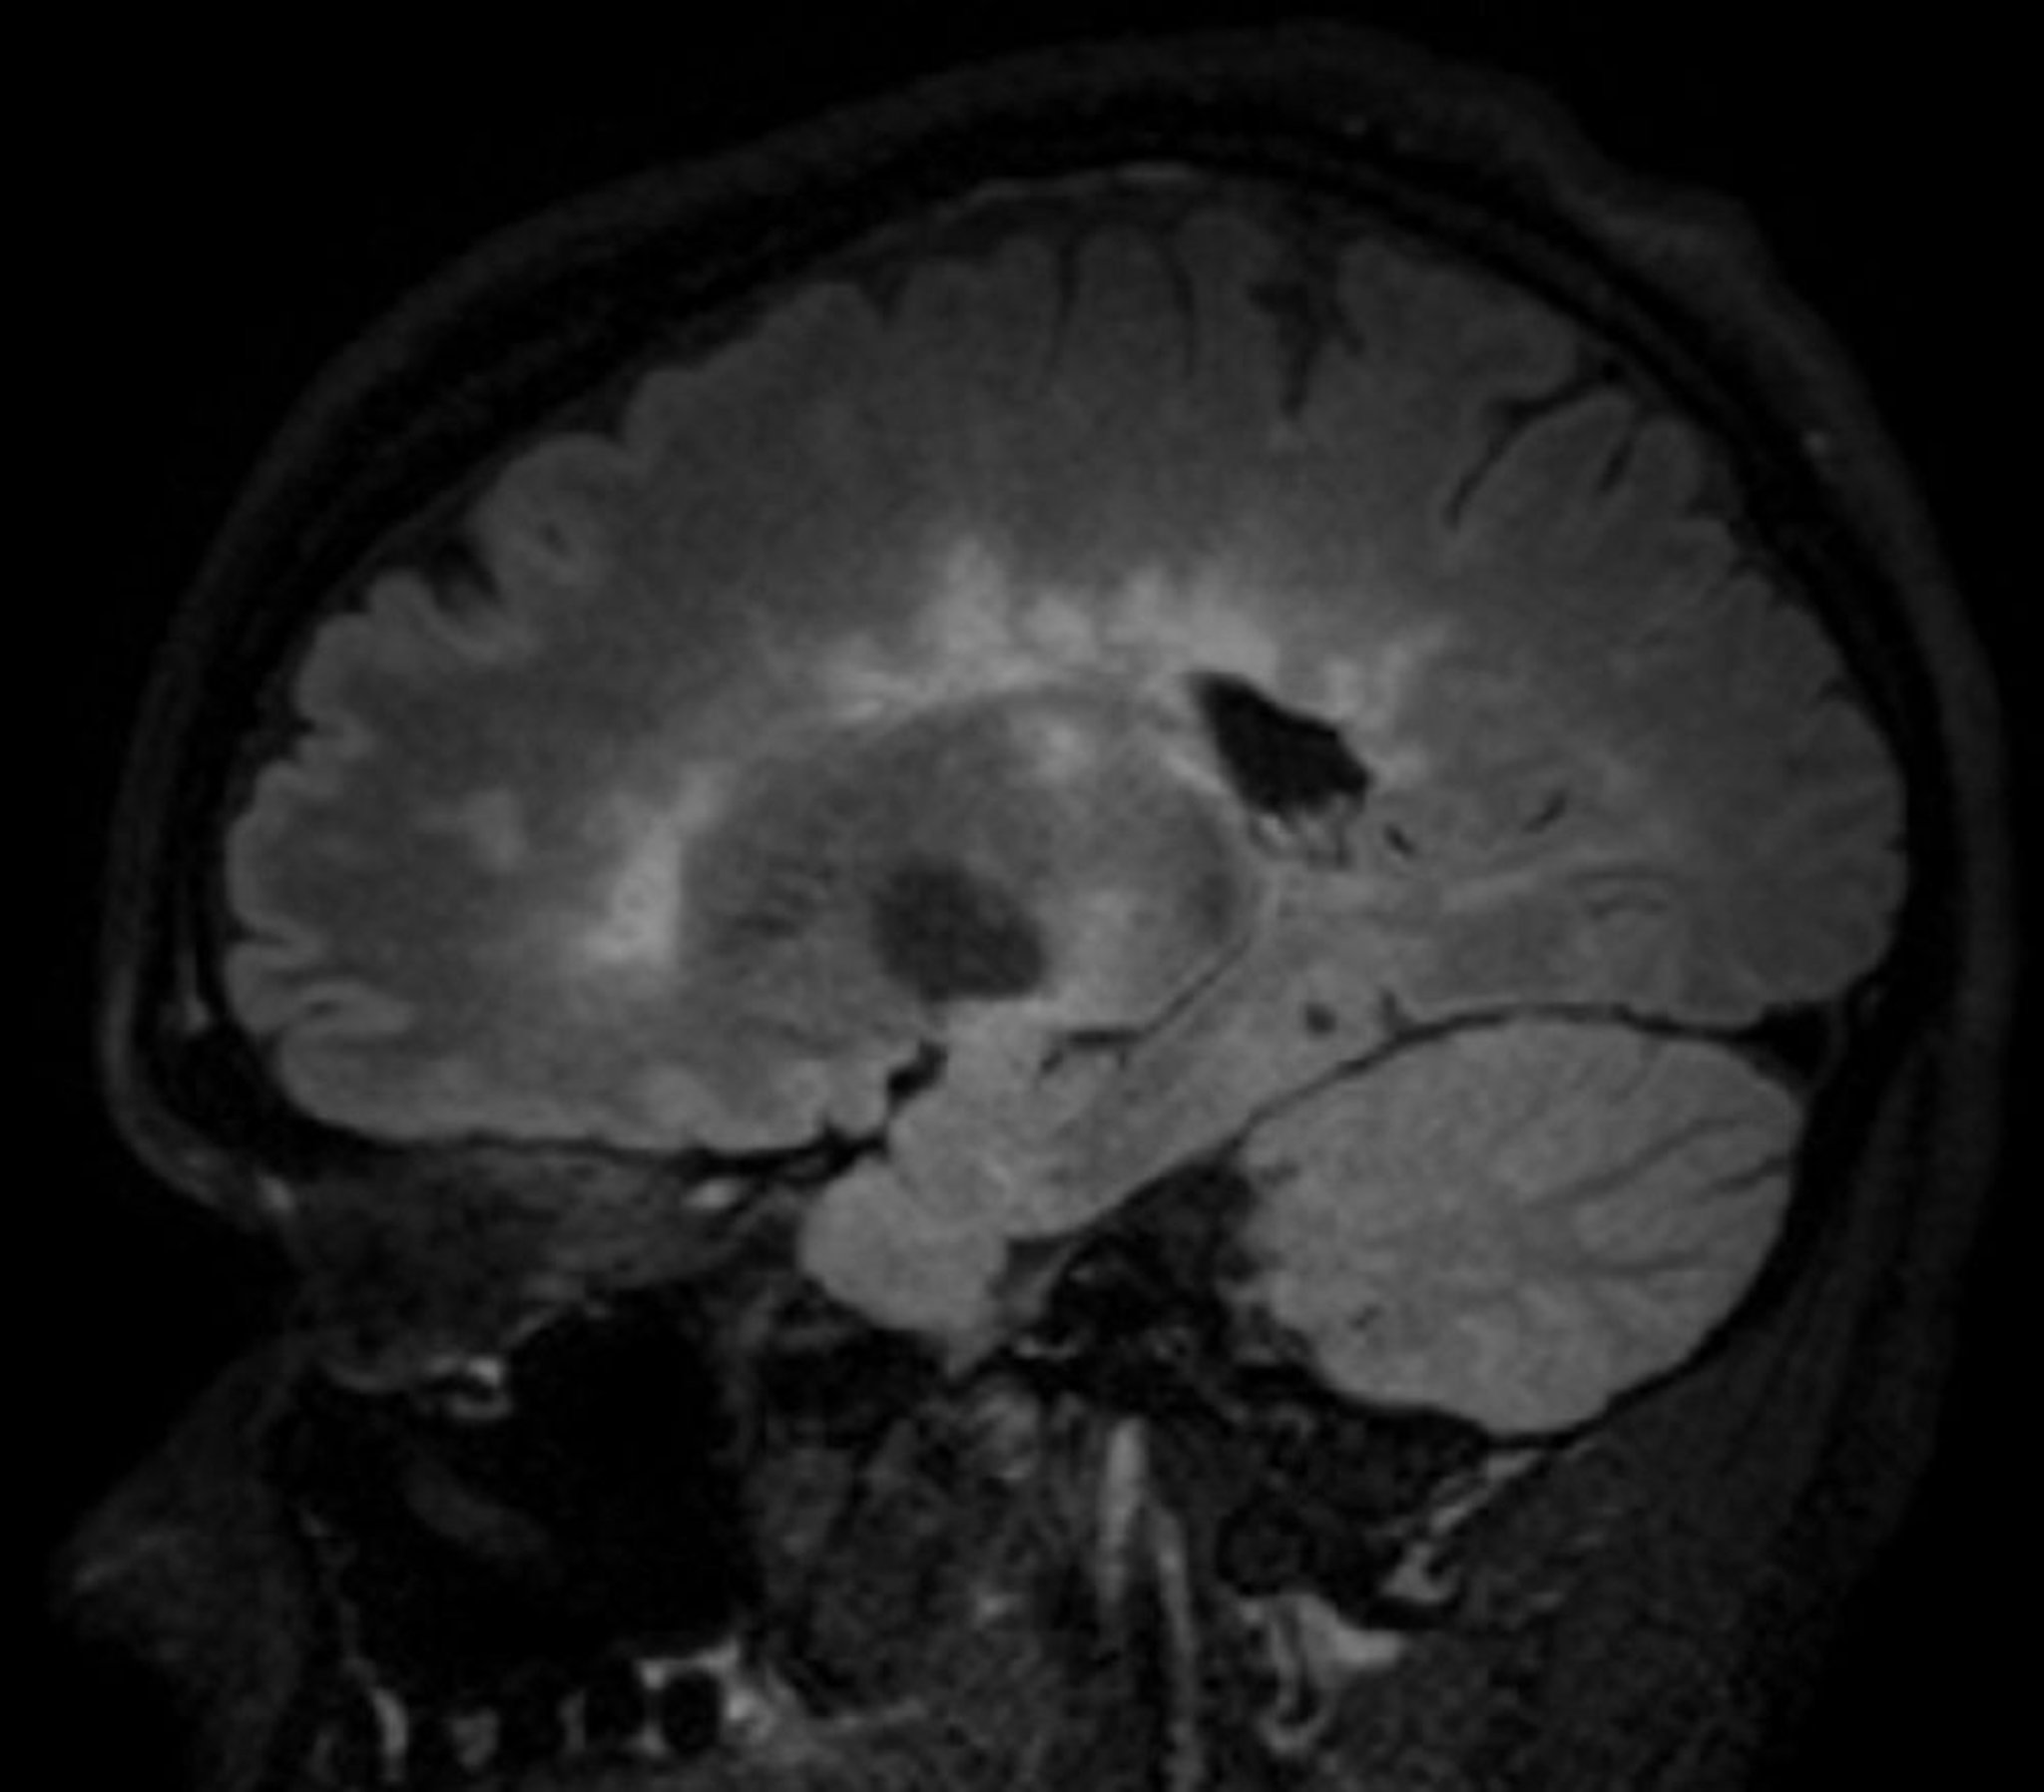

RM (FLAIR [fluid-attenuating inversion recovery]) nella sclerosi multipla

Questa immagine mostra molteplici lesioni iperintense della sostanza bianca viste in un'incidenza sagittale del cervello in un paziente con sclerosi multipla. Questo risultato è talvolta chiamato dita di Dawson.